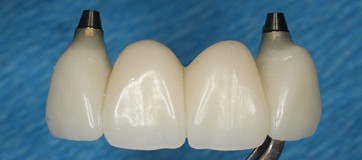

A milled PMMA temporary shell was designed with an ideal screw access and built-in critical zone for the emergence profile. The screw access area was designed to fit an the average diameter of a temporary abutment. This design decreases excessive adjustment of the shell.

The design of the temporary shell also included indexing wings which function to align the planned temporary restoration to the proper 3D orientation with perfect proximal contacts and no- centric occlusion restorations.